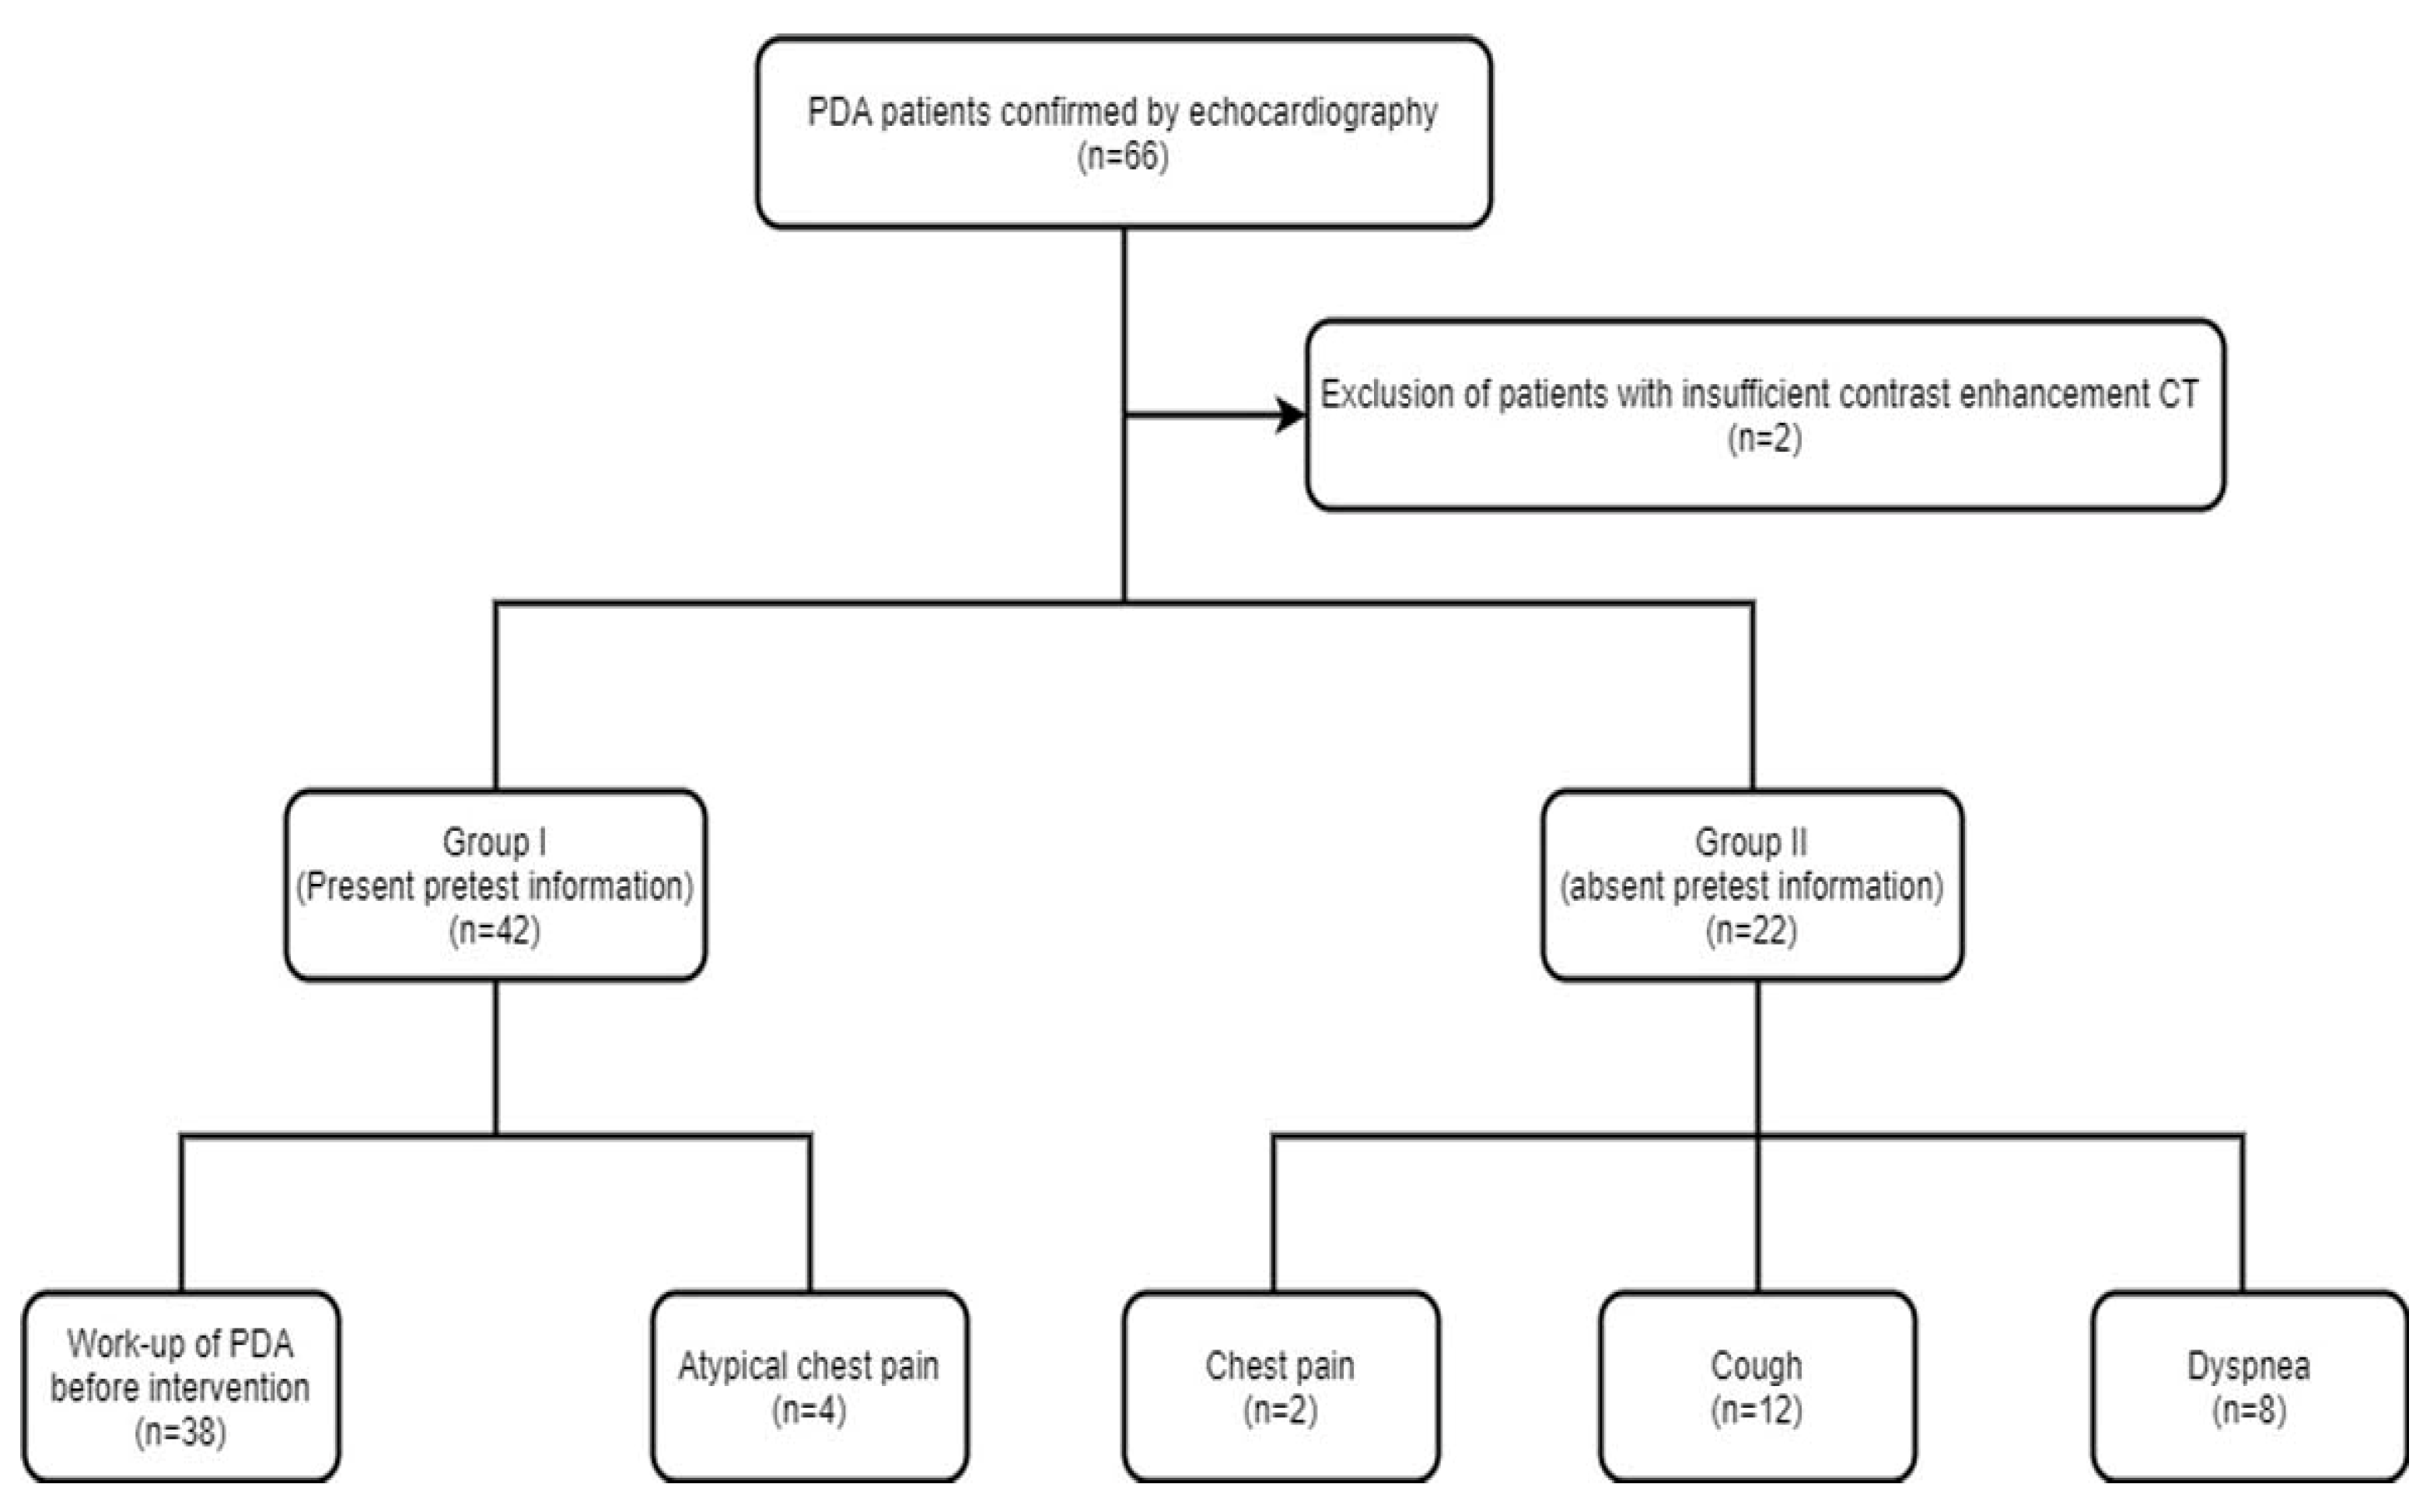

2. Materials and Methods

2.1. Study Population